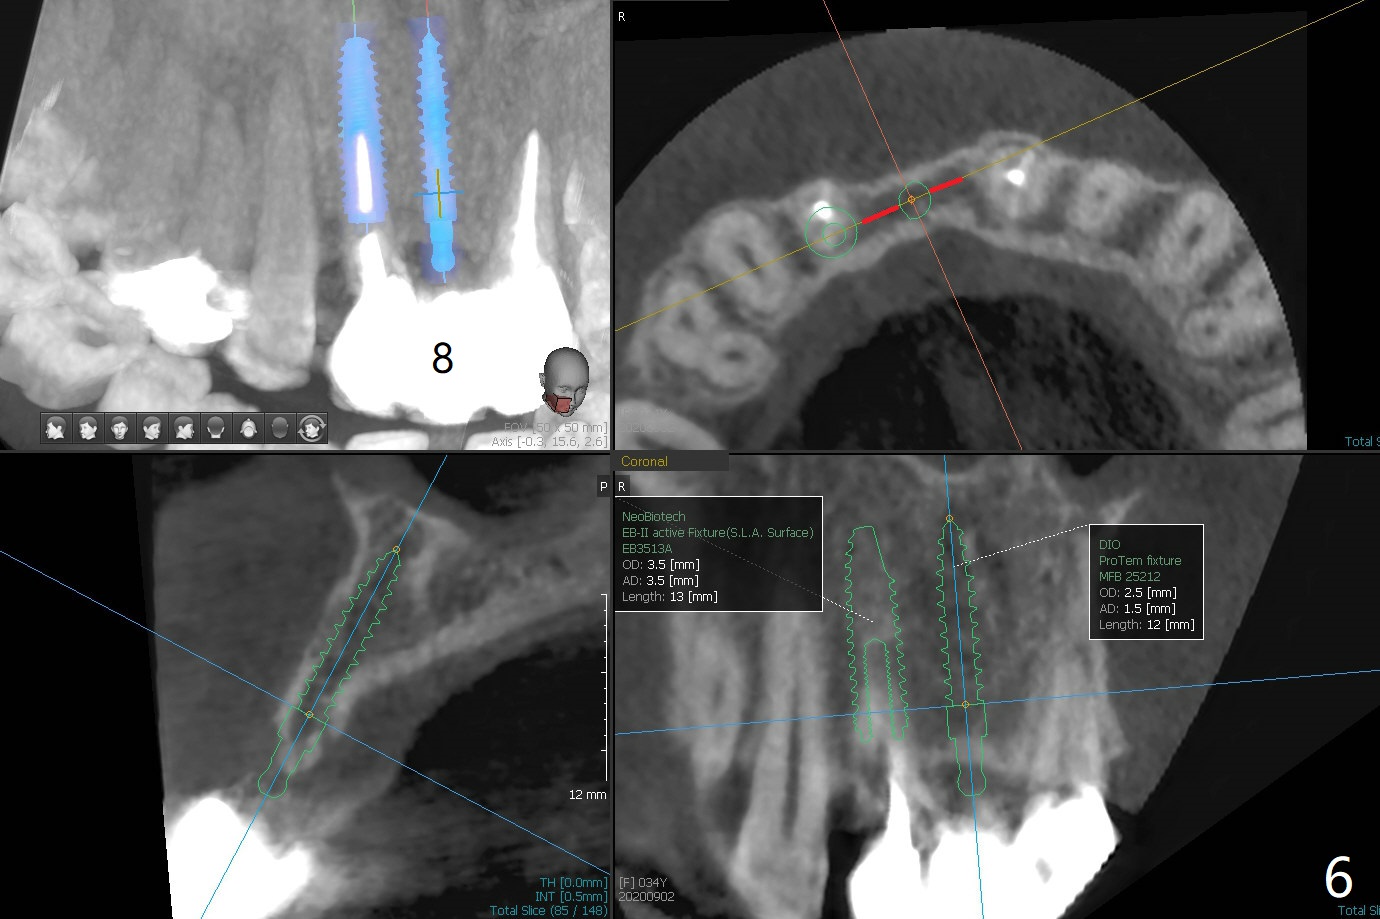

A 34-year-old woman requests fixing the failed anterior FPD (Fig.1). The edentulous alveolus looks thin; 1-piece implant may be indicated at most. A regular narrow 2-piece implant will be placed at the lateral incisor (Fig.2). CT is necessary for treatment planning. Impression has been taken for stent fabrication. 34岁女,一年半前来诊所(图一,二(侧切牙种植,做悬臂桥,暂时保留左上1牙冠)),希望修复右上门牙桥。现在终于要求立即做,基牙处牙龈红肿 (图三(今天做深洗)),牙桥颊侧移位(图四),侧切牙(7号牙)牙槽嵴也不是很宽,植入3.5毫米植体(两段式, IBS)还勉强(图五)。为了简化,避免悬臂桥,我还想在中切牙(8号牙)无牙处植入一段式2.5毫米植体(图六),适当做些牙槽嵴劈开(图六右上图:红线; from IBS cassette)。这周末徒手植入,她离开时应该有固定临时修复物。

一段式植体似乎不美观,其实它适用于近中远中空间狭窄地方,如这个病例,而两段式植体显得太粗,没有空间形成牙龈乳头,况且容易以后导致植牙周围炎。即刻临时牙冠手术第一天就起到美观作用,术后三四个月中反复调整,为永久性牙冠奠定基础。以下手术步骤就是为了这个目的。在中切牙之间切断牙桥,为右上1狭窄牙槽嵴拍摄照片(颊侧,咬合面观),切口,铬羊肠缝线牵拉,外科车针去除尖端牙槽嵴直到后者宽度达到~ 3毫米,使用1.2毫米一段式钻头,8 毫米,插入一个已经折断同样大小车针作为定位;拔除侧切牙,拍摄各式各样刮匙和肉芽组织去除器械,用1.6毫米钻头在腭侧骨板钻洞,深度9毫米,拍摄术中第一张根尖片;在中切牙处使用片状骨凿稍做骨扩张,必要时旋转式扩大器,之后完成牙槽嵴下植体放置,侧切牙牙槽窝以及中切牙术野插入无絮棉布,做必要基台制备,使用成品临时牙冠制作两个分开牙冠,确保牙龈下边缘,取出棉布,植骨,放置PRF膜,插入临时牙冠,尤其是中切牙牙冠和骨粉将改善颊侧,腭侧(与图四箭头对比)饱满度,最后缝合,调整咬合。7,8号牙骨质密度分别为700和 500单位(图七,八)。